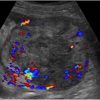

RCC

» Thông tin: Nữ giới – 69 tuổi.

» Lâm sàng: Đái máu.

# Ung thư biểu mô tế bào thận phải (Renal cell carcinoma – RCC) / Huyết khối tĩnh mạch chủ dưới.